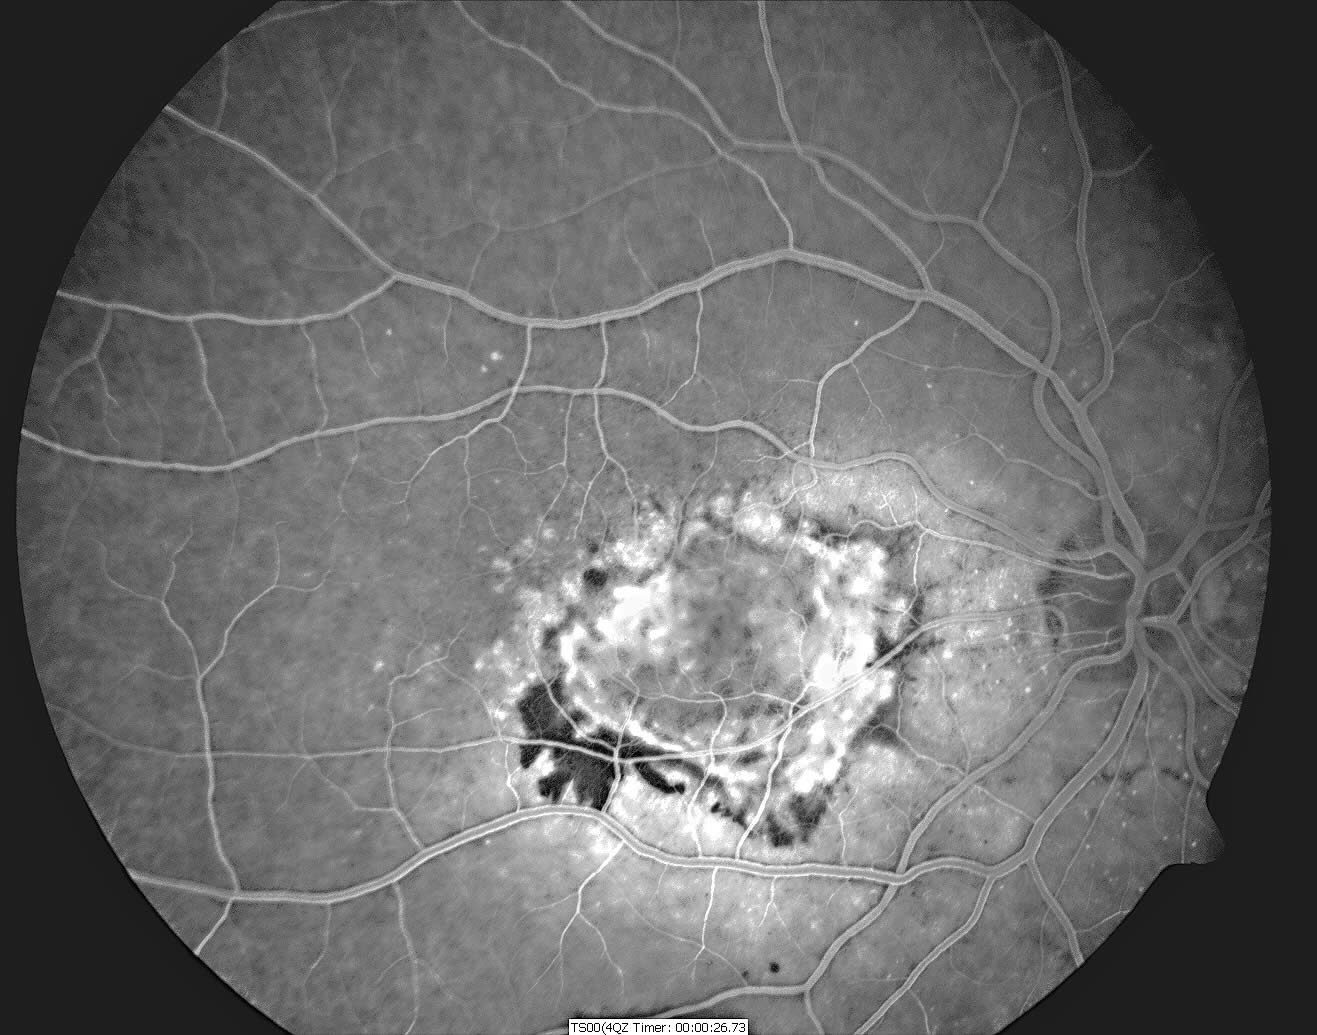

The definitive investigation is fluorescein angiography. Fluorescein dye is injected intravenously, and as it circulates around the eye, a series of photographs are taken of the retina using a blue light to illuminate the retina. The fluorescein then emits green light, which is detected by the camera. Unlike normal retinal blood vessels, the CNV leak fluorescein, and this can be seen as a bright area in the angiogram photos (see Figure 3). The fibrovascular membranes are classified as either ‘classic’ (well-defined on fluorescein angiography), or ‘occult’, if leakage is seen but the membrane is not well-defined. New digital fundus cameras, which are expensive to buy but have very low running costs, are making fluorescein angiography more accessible.

Figure 3. The fluorescein angiogram of the same eye shows the membrane much more clearly. The black area corresponds to the haemorrhage, and the membrane is seen as a bright irregularly shaped area of approximately two disc diameters’ width. © David Yorston